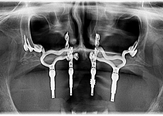

Subperiostalni implantat je individualizirana titanska konstrukcija koja se ne ugrađuje unutar kosti poput klasičnog implantata, već se postavlja iznad kosti, ispod sluznice i periosta.

Rezultat je titanska šablona, nešto poput “mrežice” ili “mosta” koja je jedinstvena za svakog pacijenta.

Ovakav individualizirani pristup osigurava da implantat maksimalno naliježe na kost i pruža optimalnu stabilnost.

Druga bitna prednost je to što je implantat potpuno prilagođen pacijentu. Budući da je izrađen prema 3D snimci pacijentove čeljusti, naliježe “kao saliven”. To omogućuje bolju raspodjelu žvačnih sila na preostalu kost i udobnost za pacijenta. Osjećaj je vrlo sličan prirodnim zubima jer je konstrukcija stabilna.